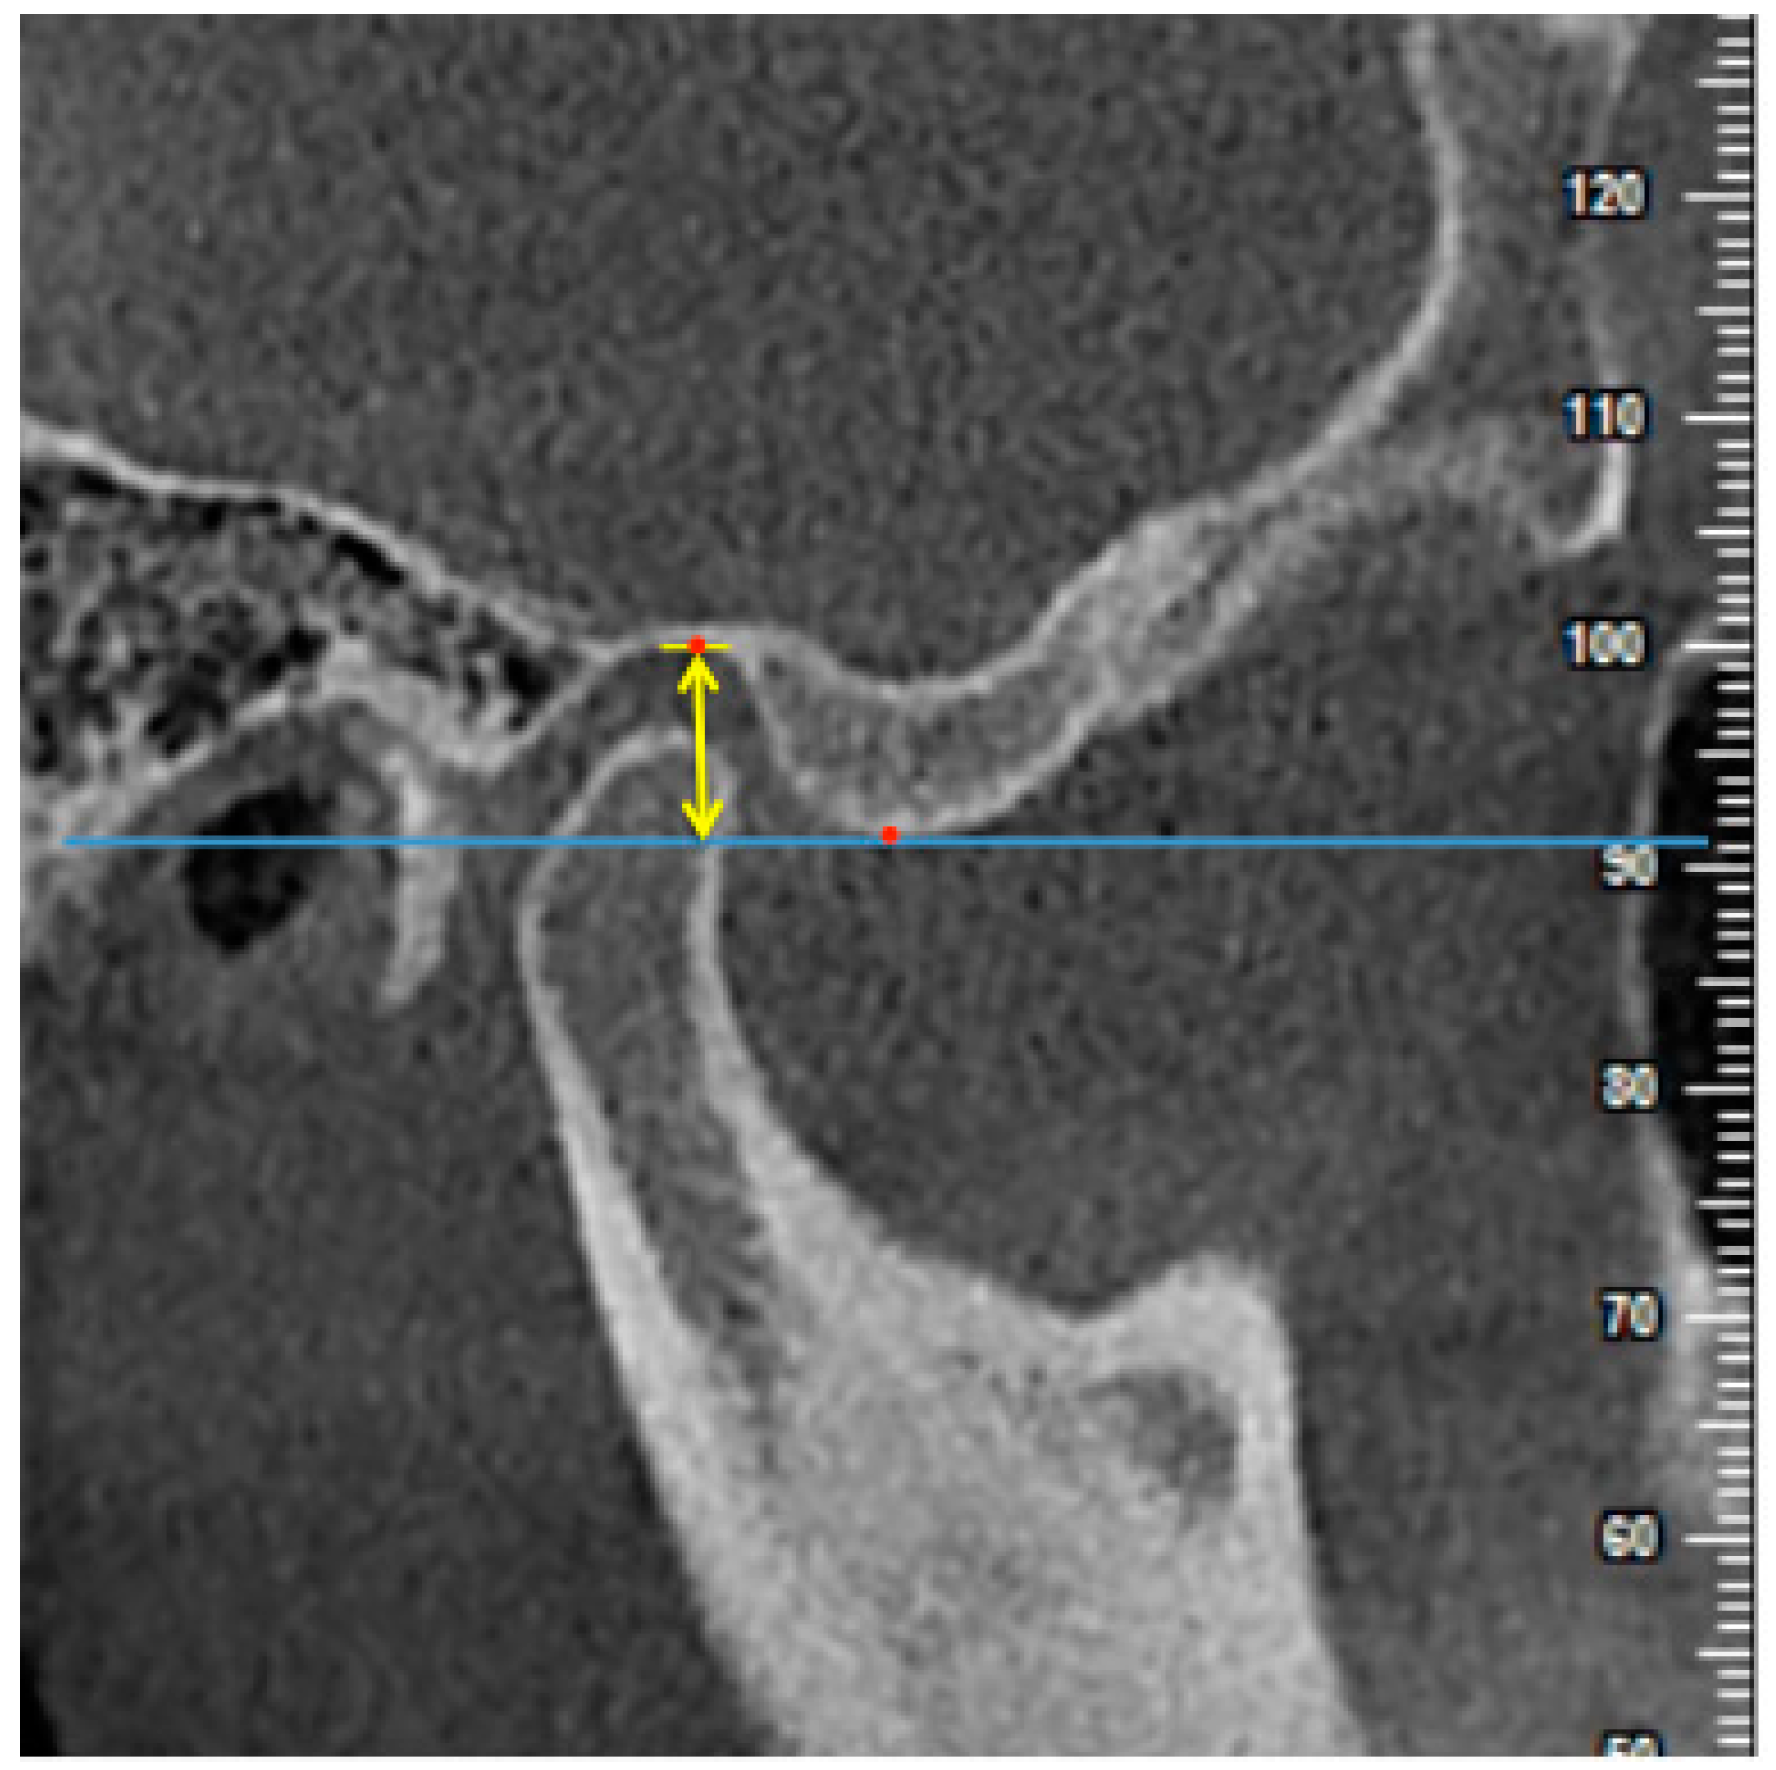

2.4. Measurements